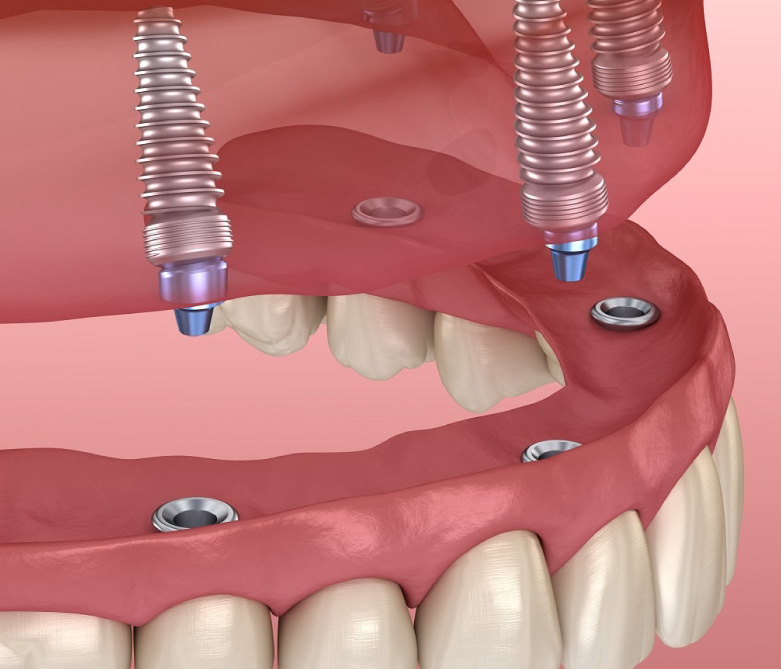

All-on-4 Implants

A technique that uses four implants to support a full arch of replacement teeth, ideal for patients with limited bone density.

All-on-6 Implants

Similar to All-on-4 but with six implants, providing enhanced stability for a full arch of replacement teeth.